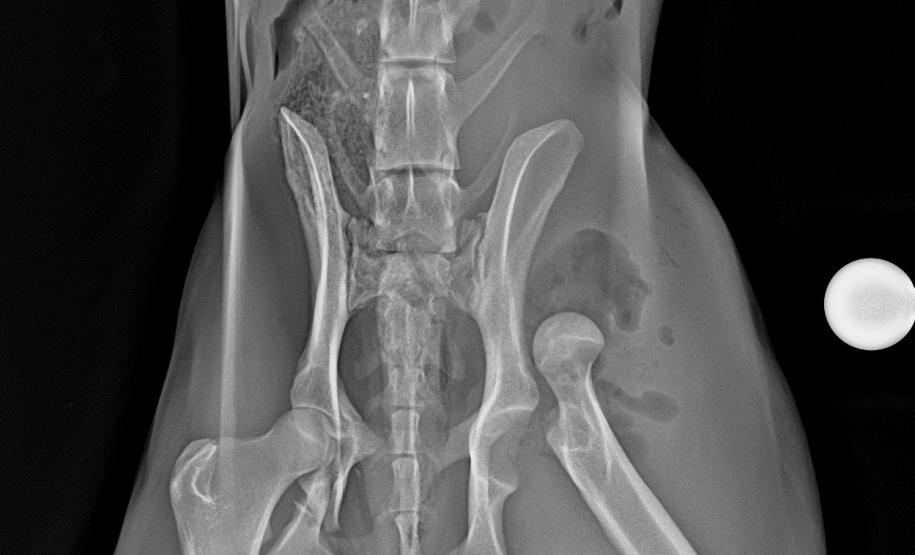

Técnicos do Instituto Água e Terra (IAT) da região dos Campos Gerais resgataram nesta quinta-feira (30) um lobo-guará vítima de atropelamento na BR-373, em Ipiranga. O animal foi encaminhado ao Centro de Triagem e Atendimento de Animais Silvestres (CETAS) em Ponta Grossa, estrutura vinculada ao instituto e que funciona em parceria com o Instituto Klimionte Ambiental. Após uma avaliação geral, exames de imagem apontaram luxação e fratura no fêmur esquerdo, e ele precisou passar por cirurgia.

O lobo-guará é macho e tem 24,3 quilos. Está sob cuidados de veterinários e ficará internado até a recuperação total, com acompanhamento integral dos técnicos do instituto. Somente com a validação médica é que poderá retornar ao habitat natural.